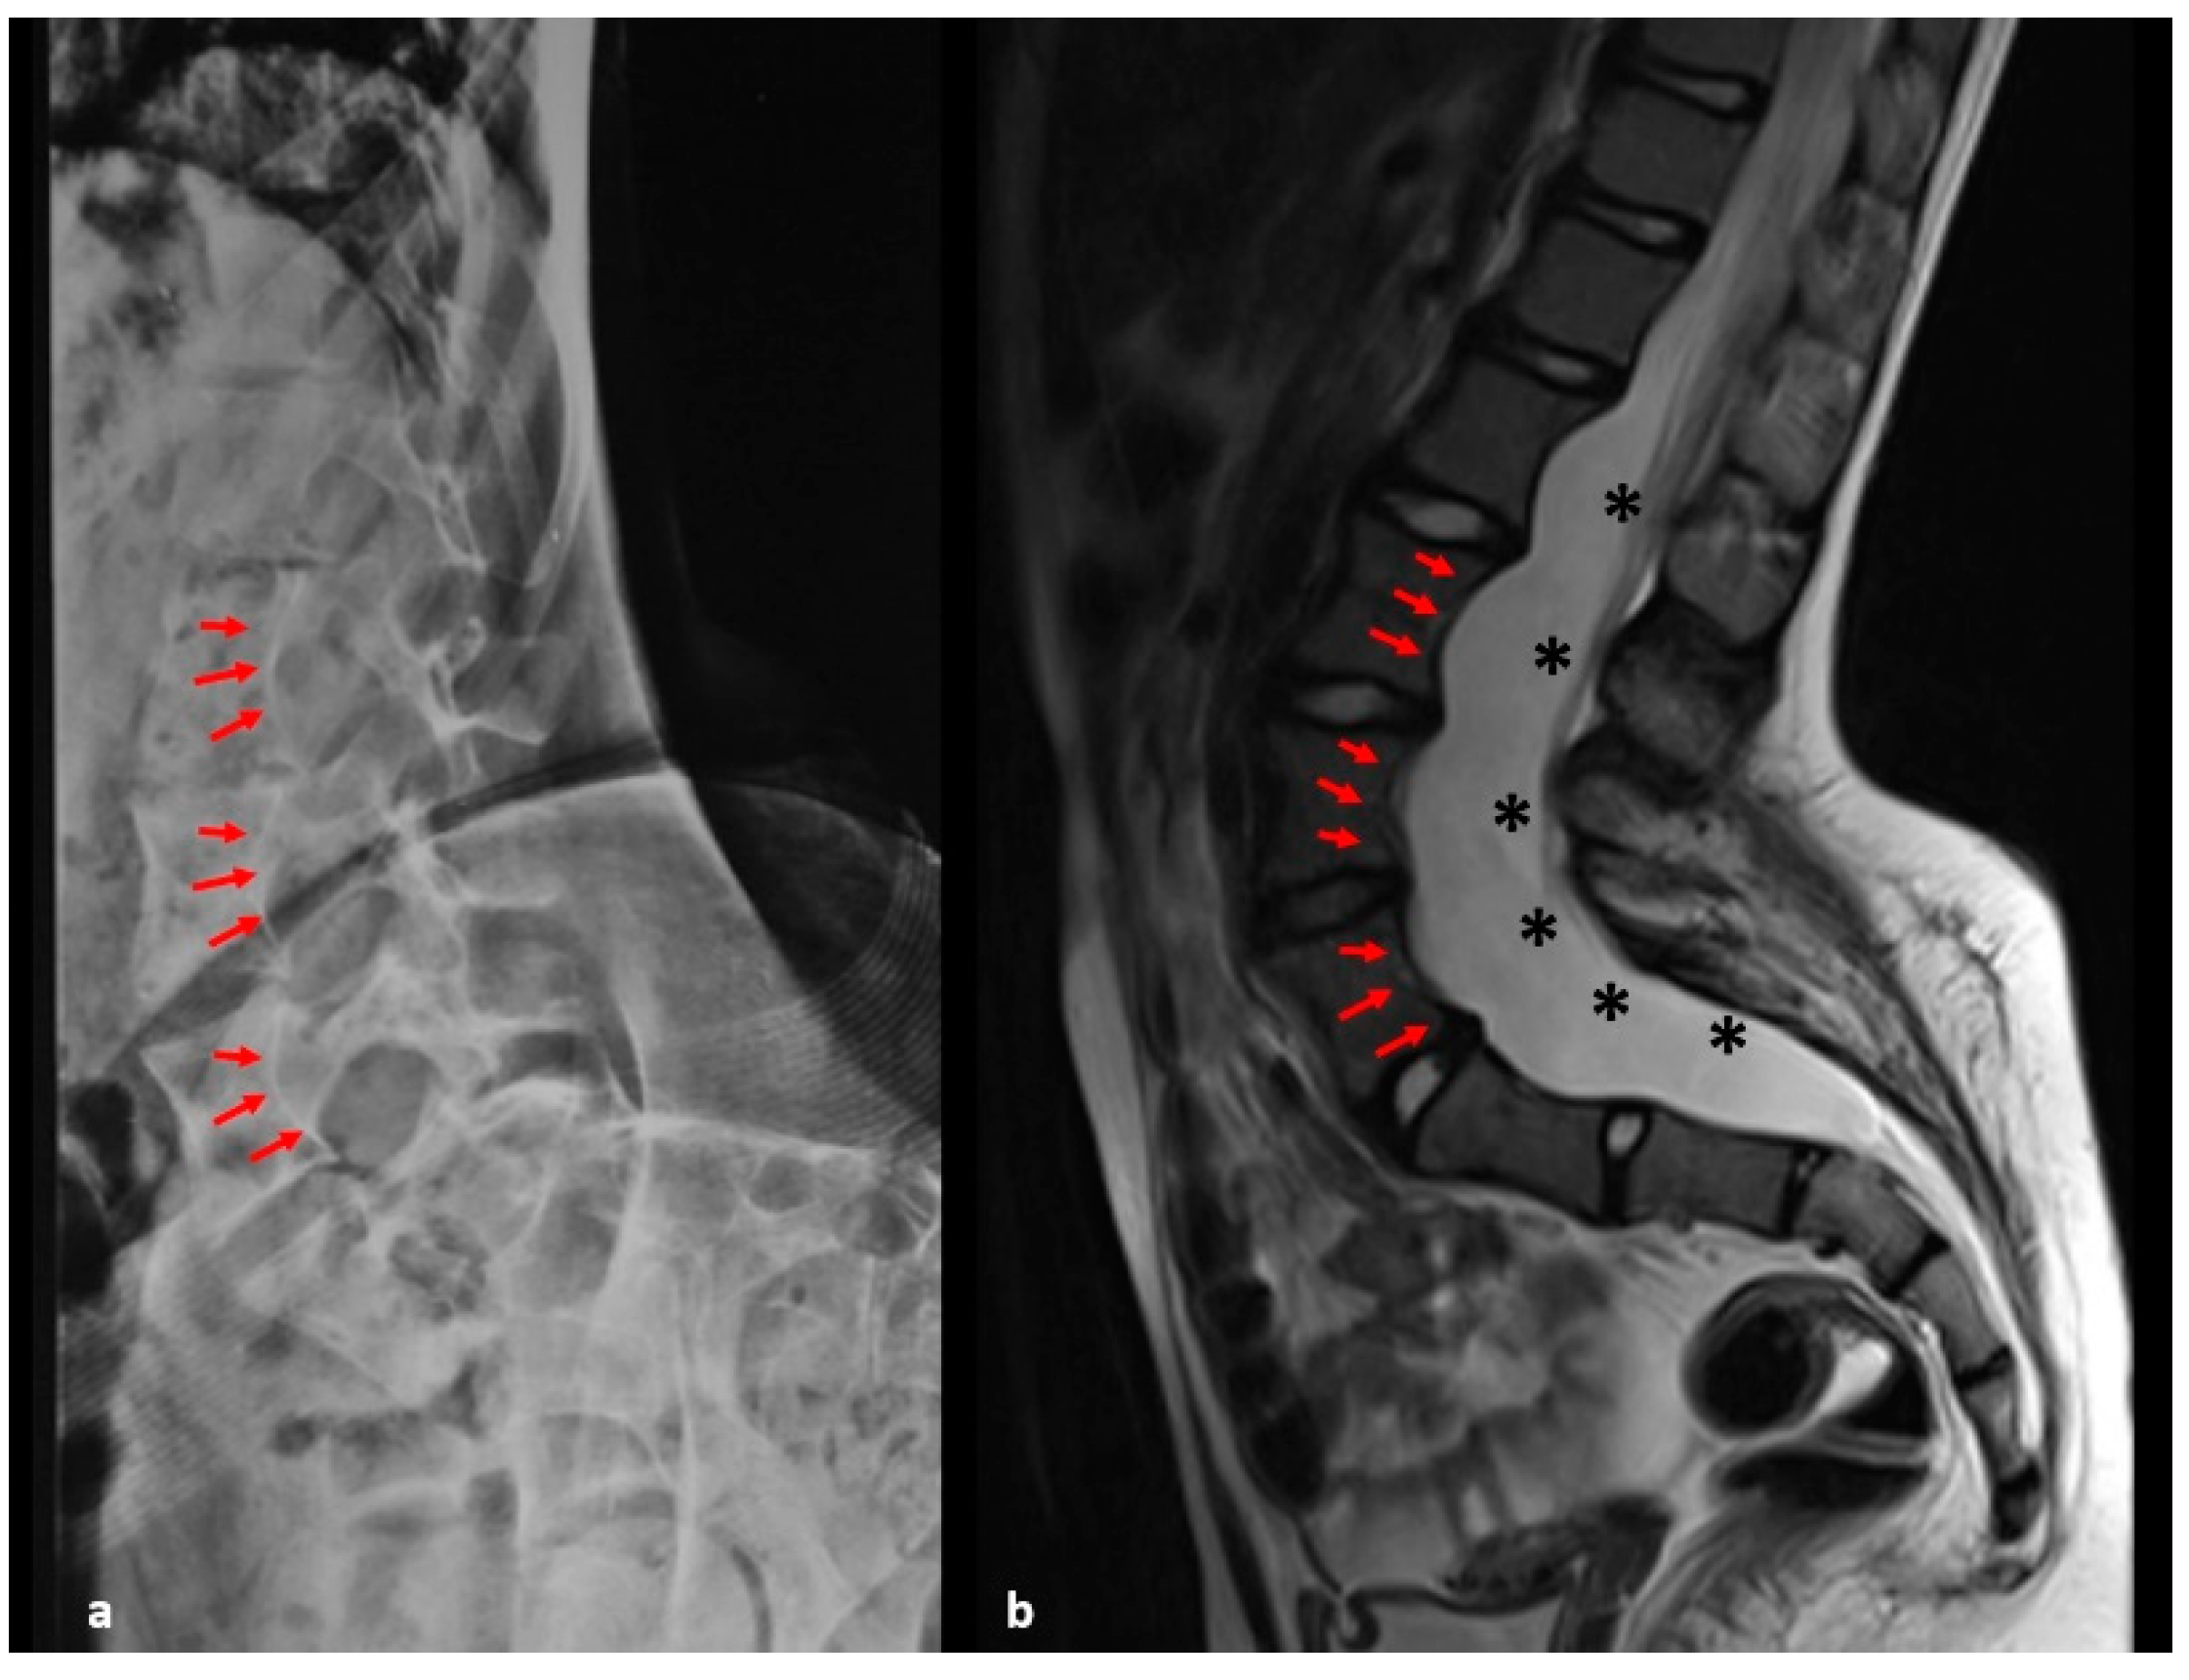

| Vertebral Scalloping (present when the depth of scalloping is >3 mm in the thoracic spine or >4 mm in the lumbar spine) |

| Dural ectasia |

| Vertebral scalloping (n) | 0 | 10 | 0.001 | |

| Dural ectasia (n) | 0 | 5 | 0.006 | |